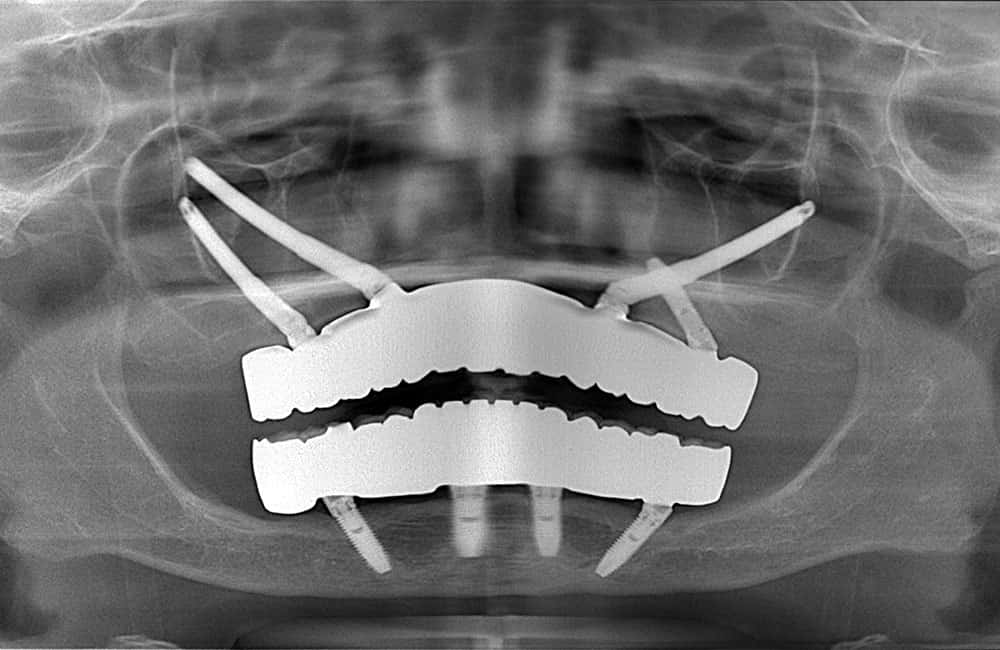

他院でザイゴマインプラント治療を受けた後、仮歯の噛み合わせが悪いため噛みづらく顔貌も変わってしまった。また頬に違和感を感じたため当院を受診。

術前のCT画像

左右のザイゴマインプラントが頬骨から大きく飛び出し頬を触ると違和感がある -

術後のCT画像

前方のインプラントは残し、他院埋入のザイゴマインプラントを除去し、同時に新しいザイゴマインプラントを適切な位置に再埋入を行っております。治療後数年経過しておりますが良好な状態を保っております。